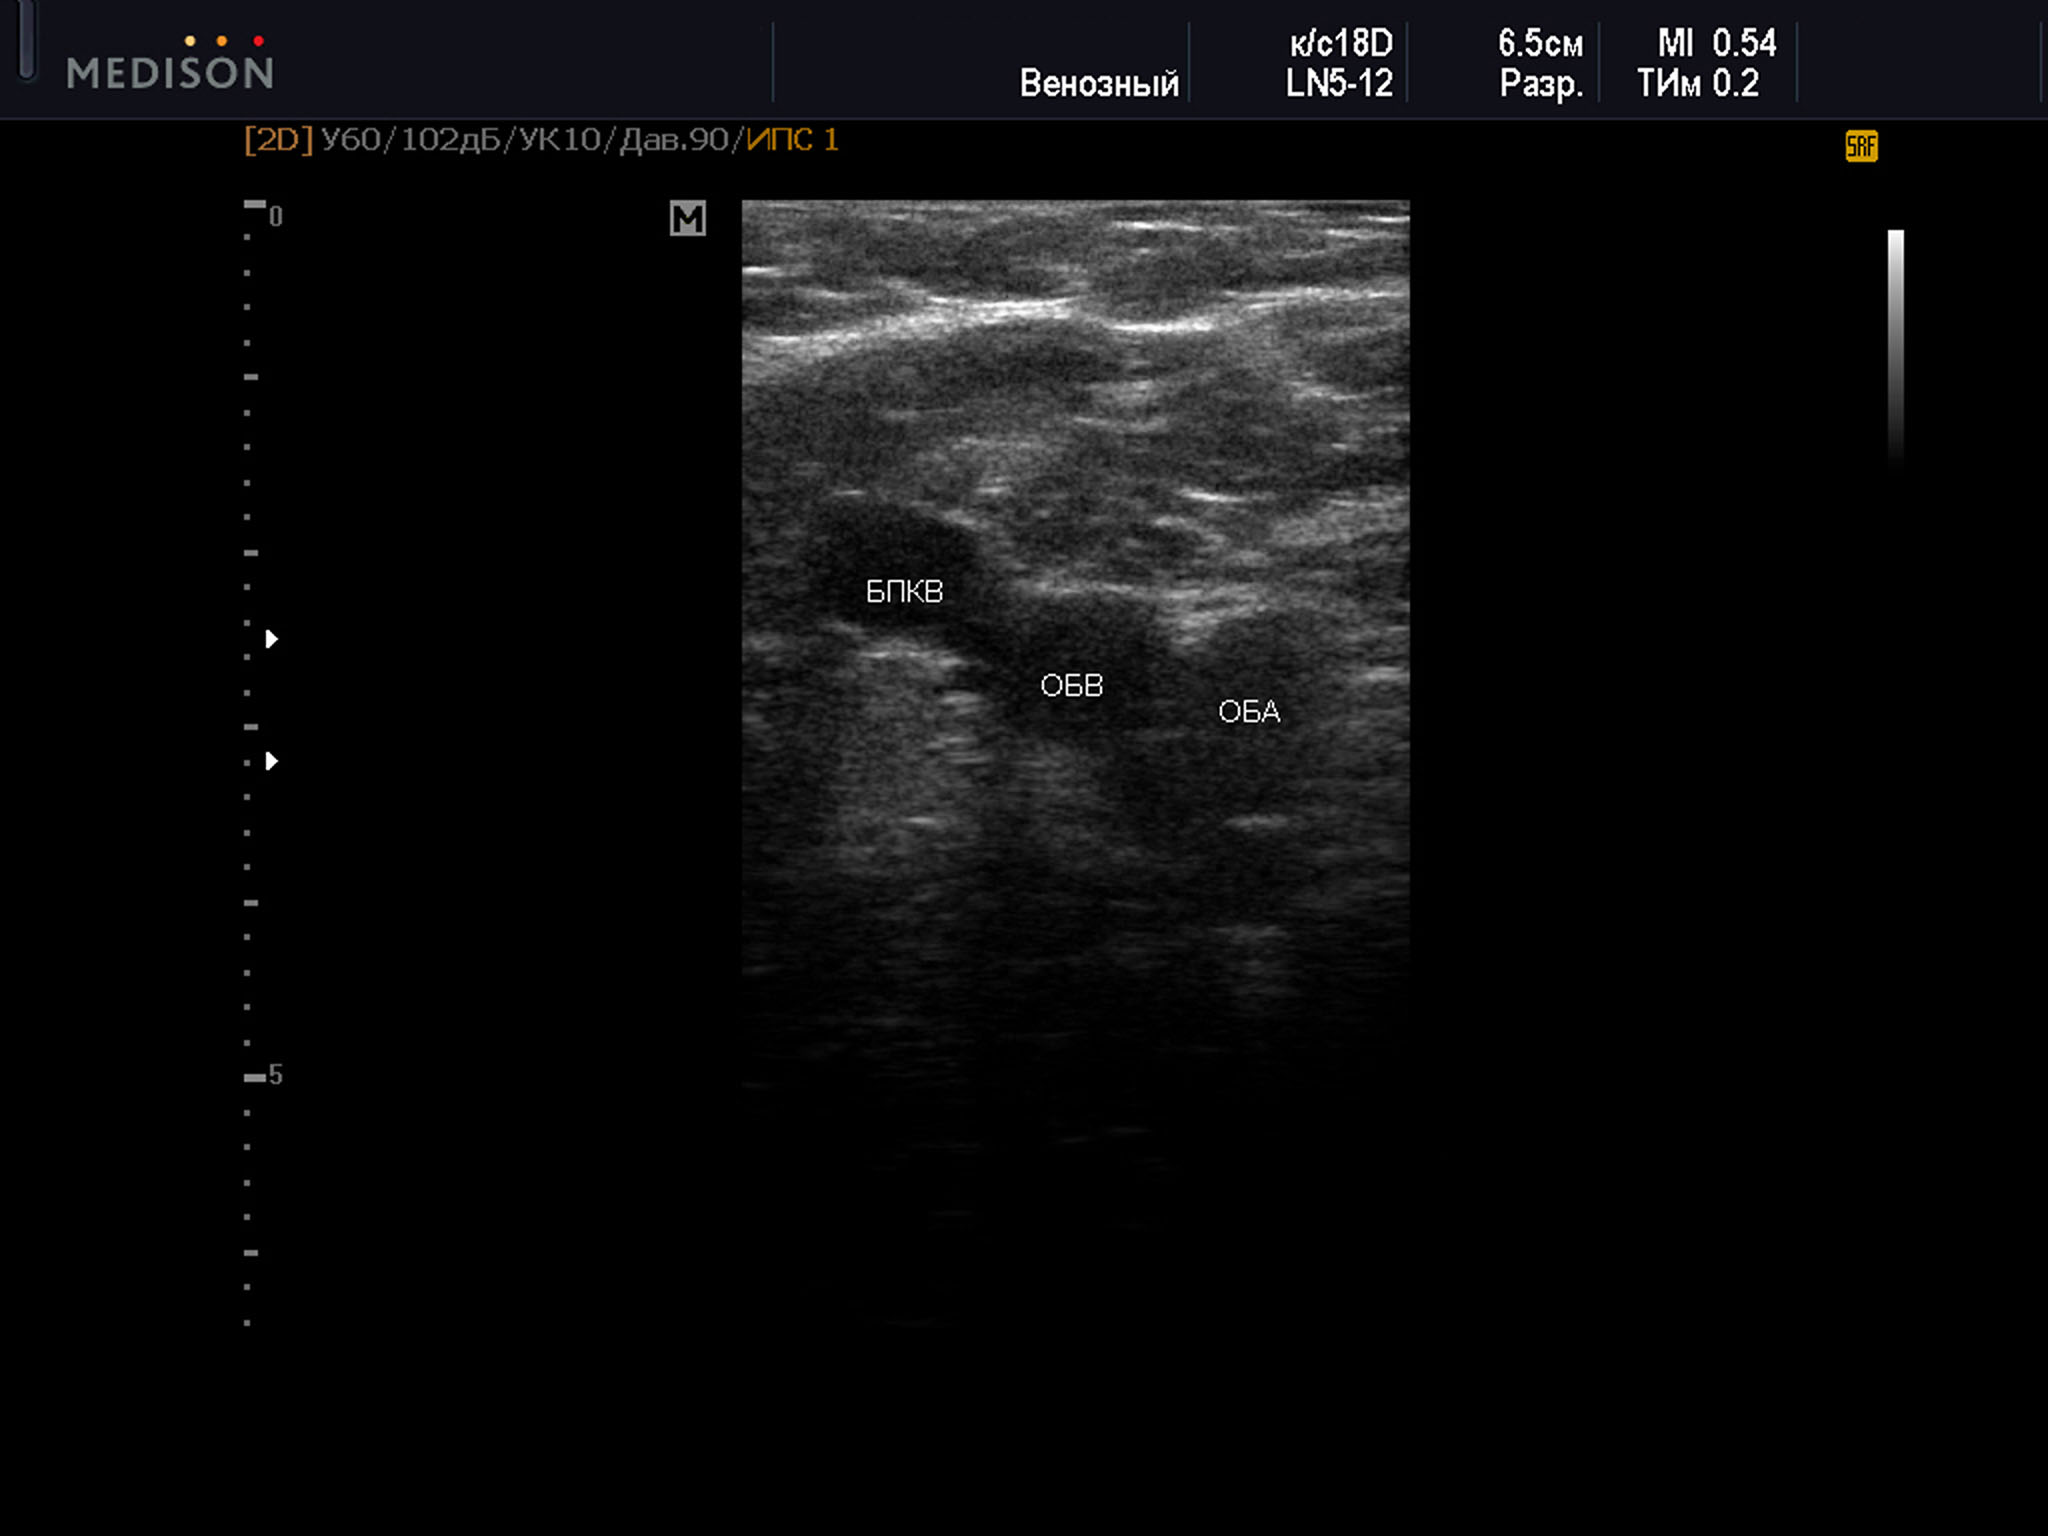

Пример диагностического ультразвукового изображения на уровне верхней трети бедра, поперечное сечение общей бедренной вены и общей бедренной артерии, Тип 2 взаимного положения сосудов

SonoAce R7, линейный датчик, мужчина, 55 лет.

ОБА – общая бедренная артерия; ОБВ – общая бедренная вена; БПКВ – большая подкожная вена бедра

2 тип оказался самым распространенным, составляя 33% от общего числа наблюдений. При этом в 36% был диагностирован справа, и в 29,8% — слева. Среди женщин данный тип встречался в 33,8% наблюдений. Справа данный вариант положения сосудов был выявлен в 35,8%, а слева в 31,7%. В группе мужчин представленный вариант расположения сосудов определялся в 31,8% всех наблюдений. Значительно чаще был выявлен справа — 36,2%, а слева в 26,8%. Возраст всех участников с данным типом положения сосудов был от 28 до 79 лет — 54,7±13,3 года, среди женщин возраст был от 28 до 79 лет — 52,9 ± 13,8 лет, возраст мужчин был от 28 до 78 лет — 57,0 ± 11,8 лет.